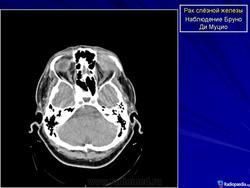

Диагноз устанавливают только после гистологического исследования. Предположительный диагноз может быть установлен на основании анализа клинических симптомов и результатов инструментального исследования. При рентгенографии на фоне увеличенной в размерах орбиты выявляются участки костной деструкции, чаще в верхненаружной, верхней и наружной стенках орбиты. Компьютерная томография позволяет определить протяженность тени опухоли, неравномерность ее краев, распространение в прилежащие экстраокулярные мышцы и неравномерность контуров костной стенки орбиты или ее полное разрушение, а ультразвуковое исследование — лишь наличие тени опухоли и ее плотность. Радиосцинтиграмма орбиты при аденокарциноме характеризуется увеличением коэффициента асимметрии, свойственного злокачественным опухолям. Информативна дистанционная термография, особенно с сахарной нагрузкой. Уточнить диагноз помогает дооперационная тонкоигольная аспирационная биопсия.